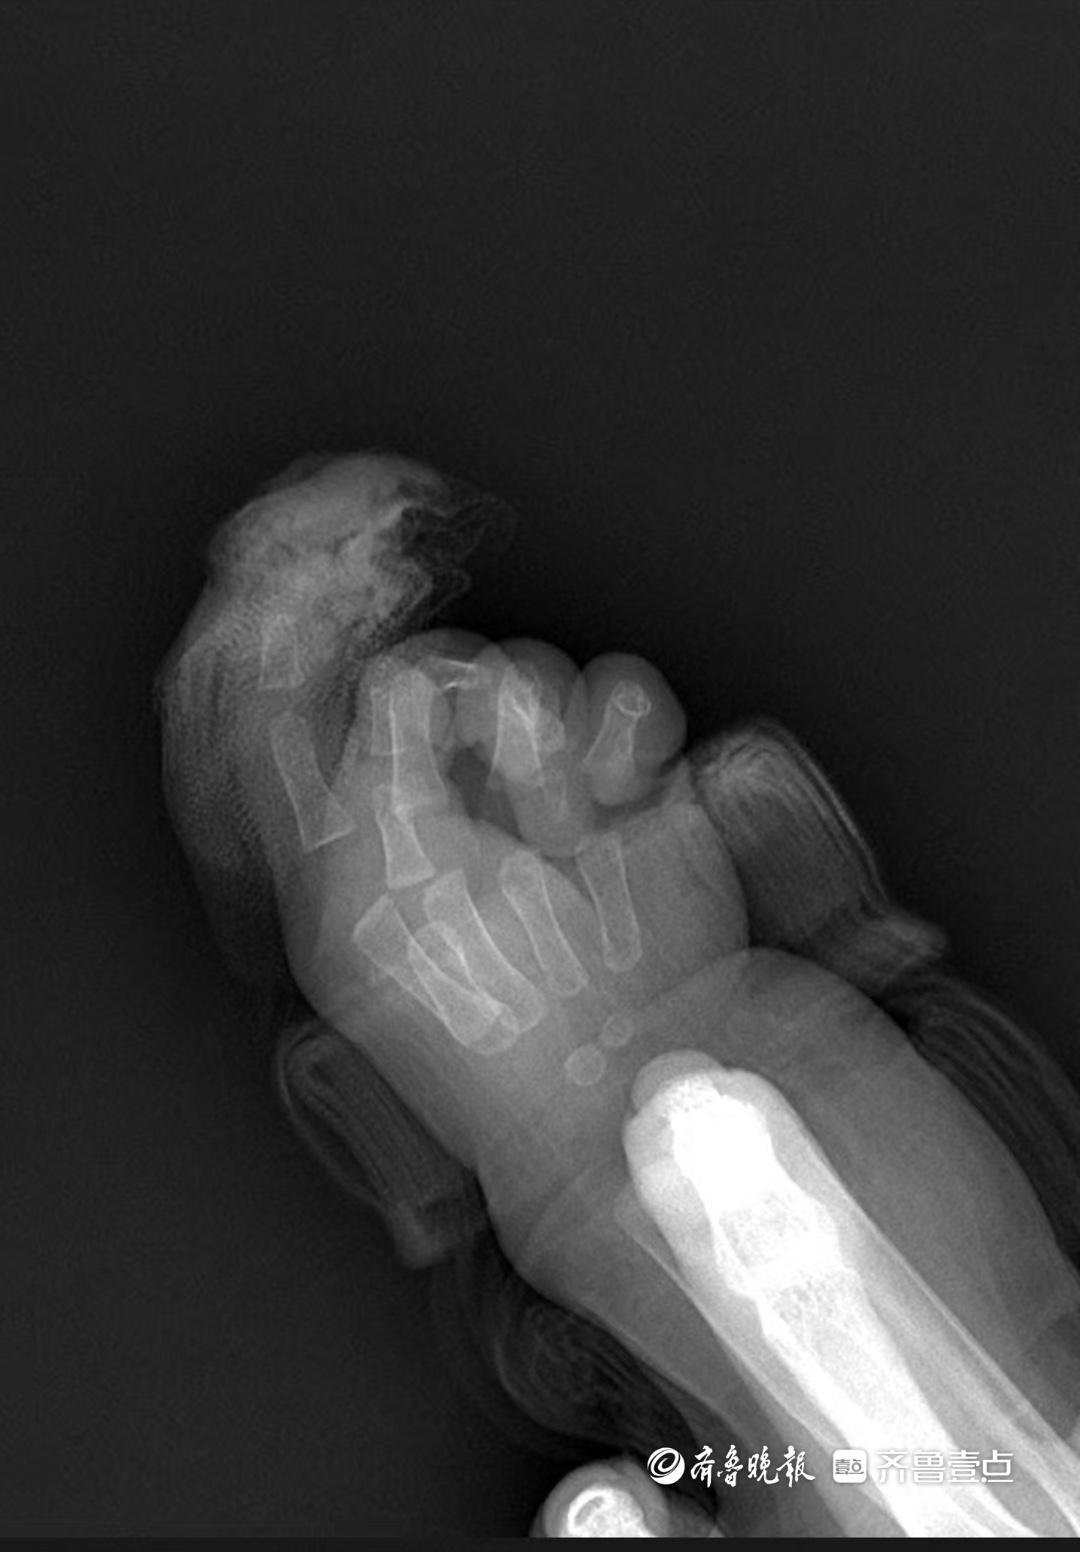

“急診就診時間是9時22分,同步啓動術前準備。”手及上肢外科主治醫生王思月回憶,急診團隊第一時間爲芙芙止血、抽血、做心電圖和拍片,“孩子傷口還在滲血,更換了3次紗布,同時輸液,避免脫水。”

按醫院流程,斷指被立即送至手術室專用冰箱冷藏。“家屬拿來時保存得很好,低溫能讓細胞代謝速率降低至常溫的1/10,爲再植爭取時間。”王思月說,這是他工作十幾年遇到的最小斷指再植患者,“整個科室都很重視,從急診到病房,所有環節都在提速。”

“手術是4月4日下午1點開始的,5點前結束,歷時3個多小時。”手及上肢外科主任胡亮回憶。爲小嬰兒接上斷指部位的血管和神經是“顯微鏡下的極限挑戰”。

“最困難的是血管太細,直徑不足0.5毫米,僅爲成人的1/5。”王思月說,他需用比髮絲還細的顯微縫線,在20倍顯微鏡下精準縫合6-8針,“間距誤差不能超過0.1毫米,神經和肌腱也得一一吻合,還有細如牙籤的鋼釘固定指骨,不能損傷骨骺板。”

胡亮坦言,手術有壓力但團隊有底氣:“我們醫生都經過專業訓練,最細的動脈能縫3針,動物實驗和大量手術積累的經驗,讓我們有信心完成。”手術中,團隊在吻合血管後持續觀察1小時,確認血運通暢才關閉創面,“比成人手術多耗時1小時,就是因爲孩子組織太精細,每一步都要更謹慎。”